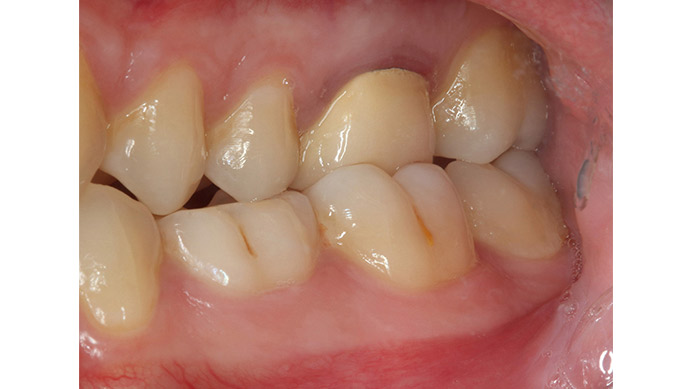

Ian es un paciente que nos cuenta su experiencia tras una intervención de cirugía periapical. Ian vino a la clínica dental IDIM con molestias en una muela superior que en el estudio radiográfico se vio que presentaba infección a causa del fracaso de una endodoncia.

Se decidió realizar una cirugía periapical para eliminar la infección y sellar las raíces con un empaste para evitar que volviera a tener problemas. Gracias a esta efectiva intervención Ian conserva su muela, lo cual es preferible, siempre que se puede, a tener que extraerla y sustituirla con un implante dental.